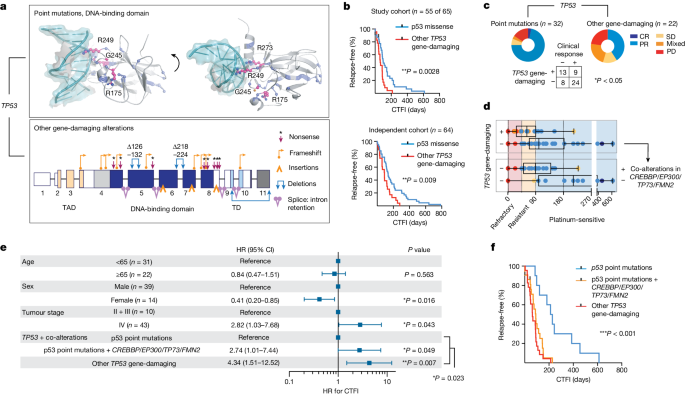

The evolutionary processes that underlie the marked sensitivity of small cell lung cancer (SCLC) to chemotherapy and rapid relapse are unknown 1 , 2 , 3 . Here we determined tumour phylogenies at diagnosis and throughout chemotherapy and immunotherapy by multiregion sequencing of 160 tumours from 65 patients. Treatment-naive SCLC exhibited clonal homogeneity at distinct tumour sites, whereas first-line platinum-based chemotherapy led to a burst in genomic intratumour heterogeneity and spatial clonal diversity. We observed branched evolution and a shift to ancestral clones underlying tumour relapse. Effective radio- or immunotherapy induced a re-expansion of founder clones with acquired genomic damage from first-line chemotherapy. Whereas TP53 and RB1 alterations were exclusively part of the common ancestor, MYC family amplifications were frequently not constituents of the founder clone. At relapse, emerging subclonal mutations affected key genes associated with SCLC biology, and tumours harbouring clonal CREBBP / EP300 alterations underwent genome duplications. Gene-damaging TP53 alterations and co-alterations of TP53 missense mutations with TP73 , CREBBP / EP300 or FMN2 were significantly associated with shorter disease relapse following chemotherapy. In summary, we uncover key processes of the genomic evolution of SCLC under therapy, identify the common ancestor as the source of clonal diversity at relapse and show central genomic patterns associated with sensitivity and resistance to chemotherapy.

Tumour specimens and clinical data

We collected 160 tumour specimens from 65 patients with SCLC under institutional review board approval and performed whole-exome, genome and transcriptome sequencing of samples with an average tumour purity of 85% (Fig. 1a–c and Supplementary Tables 1 – 3 ). We most frequently sampled the primary lung tumour, pulmonary lymph nodes, liver, pleura and brain metastases. Furthermore, patient-derived xenotransplants were established from fine-needle biopsies or circulating tumour cells (CTCs), which have been previously shown to recapitulate the genomic profiles of patients’ tumours 12 , 13 (Fig. 1a and Methods ). The histology of SCLC was confirmed in all cases; additional components of adenocarcinoma or large-cell neuroendocrine carcinoma (LCNEC) were identified in three patients (Supplementary Table 1 ). The clinical history was typical of SCLC and the majority of patients had received first-line treatment with platinum-based chemotherapy, achieving a median relapse-free interval of 88 days (Fig. 1b , Extended Data Table 1 and Supplementary Table 1 ). In line with clinical guidelines 14 we grouped patients according to their duration of response to first-line chemotherapy, referring to the chemotherapy-free interval (CTFI) of 45, 90 and 180 days (Fig. 1b ). At relapse, 80% of these patients ( n = 44 of 55) received additional lines of therapy, which included other chemotherapeutics or treatment with anti-PD-1 and/or anti-CTLA-4 ICIs (Supplementary Table 1 ).

a , Tumour sites sampled from 65 patients with SCLC. Frequently sampled sites are highlighted in bold. Tumours were acquired either at the time of first diagnosis (treatment-naive) or following initiation of treatment (post-treatment). Tumour samples analysed as patient-derived xenotransplant (PDX) models are indicated. b , Schematic overview of the clinical course of 65 patients with SCLC. Patients were ordered according to their duration of response to first-line platinum-based chemotherapy, referring to a CTFI of 45, 90 and 180 days (National Comprehensive Cancer Network (NCCN) guidelines). Patients who, following initiation of first-line treatment, were either lost to follow-up or underwent surgical resection of the primary tumour were sorted to separate panels. The treatment administered to each patient is annotated and the clinical response is described as either complete response (CR), partial response (PR), stable disease (SD), progressive disease (PD) or mixed response (PR/PD). A detailed description of all clinical characteristics is provided in Supplementary Table 1 and Methods . c , Schematic overview showing the analysis of paired, patient-matched tumour sites: paired studies of spatially distinct tumours at the time of first diagnosis (treatment-naive, n = 16); paired studies of tumour sites pretreatment and during treatment ( n = 5) or at clinical relapse following completion of first-line platinum-based chemotherapy ( n = 42); paired analyses of spatially distinct tumour sites at relapse ( n = 14); and analyses of tumours acquired before and after subsequent lines of treatment with ICIs ( n = 7). The scheme shows tumour sites in the lung, referring to primary and metastatic sites (larger and smaller red circles, respectively). LN, lymph node.

We analysed at least two tumour samples per patient, obtained at either single or multiple time points throughout the course of treatment. For interpatient comparisons we focused on paired studies of tumours acquired under distinct scenarios throughout the clinical course of the patients: (1) spatially distinct tumour samples in the treatment-naive setting at the time of first diagnosis ( n = 16); (2) temporally distinct tumours acquired at first diagnosis before initiation of therapy and either during first-line platinum-based chemotherapy ( n = 5) or following completion of chemotherapy ( n = 42); (3) spatially, but not temporally, separate tumours analysed solely at the time of relapse ( n = 14); and (4) tumours obtained before and after subsequent lines of treatment with immunotherapy ( n = 7) (Fig. 1c , Extended Data Table 1 and Methods ).

We therefore proposed that the overall genomic make-up of the common ancestral clone is the main driver of the sensitivity of patients to first-line chemotherapy. TP53 and RB1 alterations were universally part of the common ancestral clone, and we sought to further classify alterations in both genes according to their impact on the functionality of the encoded protein. We distinguished between missense mutations creating a full-length protein and other somatic alterations as probably ‘gene damaging’ due to either out-of-frame transcription, early termination or larger insertions or deletions impacting protein expression (Fig. 5a , Supplementary Table 11 and Methods ). When assessing clinical outcome as a function of the qualitative nature of all significant gene alterations, we thus identified a higher risk of relapse in patients with these ‘other gene-damaging’ alterations in TP53 (** P < 0.01; Fig. 5b and Extended Data Fig. 8a,b ), which had similarly been observed in other lung cancers 36 . Although patients frequently harboured point mutations in the DNA-binding domain of TP53 affecting well-known hotspot sites 28 , gene-damaging alterations occurred in 40% of patients and we confirmed either truncated or absent protein products in tumours of these patients (Fig. 5a and Extended Data Fig. 9a ). By contrast, damaging alterations constituted the vast majority of all RB1 lesions (95%; Supplementary Table 11 ) and no difference in response could be identified. Although frequently part of subclones, MYC gene amplifications were also not found to correlate with chemotherapeutic response (Extended Data Fig. 8 ). TP53 gene-damaging alterations associated with marginal or no response to chemotherapy (* P < 0.05; Fig. 5c ) resulted in a median time to disease recurrence of 63 days and almost all patients relapsed within 6 months ( n = 22 of 23; Fig. 5d ). This observation remained significant in Cox regression models considering all genomic patterns after adjusting for age, sex and tumour stage (hazard ratio 2.12 and 95% confidence interval 1.06–4.23; Extended Data Fig. 9b,c ). On the basis of these findings, we analysed an independent cohort of 63 patients with SCLC who were treated with first-line platinum-based chemotherapy, to validate the clinical relevance of destructive TP53 mutations. In this cohort, too, damaging alterations of TP53 segregated with a short duration of relapse-free interval (Fig. 5b and Supplementary Table 12 ).

a , Somatic alterations in TP53 . Point mutations mapped to the protein structure (DNA-binding domain, PDB-ID: 2AHI , top). Hotspots (pink, residues annotated), other point mutations (blue) and interaction with DNA (teal) are shown. Damaging gene alterations creating deletions, insertions and destructive transcripts are described (bottom; transactivation and tetramerization domains (TAD, TD, respectively); transcript ID: NM_000546). b , Kaplan–Meier curve of patients grouped for p53 point mutations (blue) and other gene-damaging TP53 alterations (red). Relapse-free survival refers to CTFI and is plotted for patients in this cohort who received only first-line systemic platinum-based chemotherapy (top, n = 55 of 65 patients; grey points, n = 2 censored subjects); and for an independent cohort (bottom, n = 64 patients). Log-rank test, ** P < 0.01. c , d , Clinical response (defined as complete response/partial response) to first-line systemic chemotherapy for n = 54 of 65 patients grouped for p53 point mutations and other gene-damaging TP53 alterations. Fisher’s exact test, two-sided, * P = 0.022. Patients with information available for relapse-free survival ( n = 53) were grouped for TP53 gene-damaging ( n = 22) or p53 point mutations ( n = 31) ( c ) and further stratified for co-alterations in CREBBP / EP300 , TP73 or FMN2 ( n = 20) or none ( n = 11) ( d ). CTFI range was 45, 90 and 180 days (red, yellow and light blue background, respectively). Boxplot, median and interquartile range, minimum and maximum values. e , f , Relapse-free survival in patients of this cohort receiving only first-line systemic platinum-based chemotherapy ( n = 55 of 65, n = 2 patients censored). e , Patients are grouped according to clonal other gene-damaging alterations in TP53 and p53 point mutations that were further stratified for significant co-alterations of CREBBP / EP300 , TP73 and FMN2 . Cox regression model adjusting for age, sex and tumour stage. HR showing the median and 95% confidence interval (CI). f , Kaplan–Meier curve ( n = 55 of 65 patients; grey points, censored subjects, n = 2); log-rank Mantel–Cox test, *** P = 0.0003.

Because some key mutations were acquired throughout the course of treatment, we next proposed that co-alterations of relevant genes might also impact patient survival. We therefore performed regression models and found that co-alterations of CREBBP / EP300 , TP73 or FMN2 increased the relative risk of disease recurrence in patients without TP53- damaging alterations, which remained significant when adjusting for clinical parameters (HR 2.74, 95% confidence interval 1.01–7.44, * P < 0.05); a similar trend was observed in the independent patient cohort (Fig. 5e,f and Extended Data Fig. 9c–e ). Furthermore, co-alterations of CREBBP / EP300 , TP73 or FMN2 suggested epistasis (Extended Data Fig. 9f ). Of note, in addition to stage, our data showed longer relapse-free survival in women not related to smoking behaviour in these patients, and may point to a sex bias (Fig. 5e and Extended Data Fig. 9g ). Taken together, our genome analyses show that TP53- damaging alterations associate with resistance to chemotherapy and that coexisting alterations of TP73 , CREBBP / EP300 or FMN2 compromise the clinical efficacy of chemotherapy in patients with SCLC—even in the absence of gene-damaging TP53 alterations.